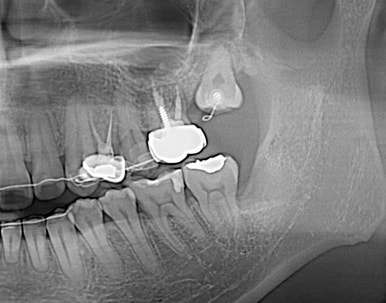

사랑니의 쓸모를 찾아서~

사랑니 교정

사랑니를 교정치료를 통해 어금니로 사용하는 케이스